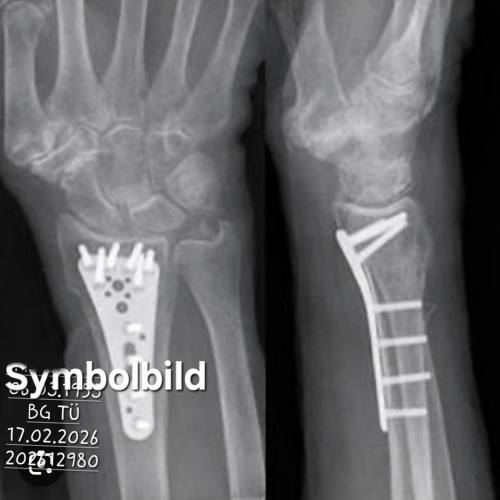

Operationverfahren

Es gibt verschiedene Verfahren, wie man den Knochenbruch letztendlich operativ behandeln.